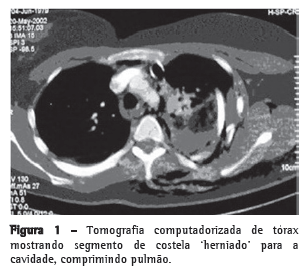

Paciente do sexo feminino, 32 anos, vítima de acidente automobilístico, que ocasionou hemopneumotórax esquerdo, contusão pulmonar esquerda e fraturas duplas do terceiro ao oitavo arcos costais esquerdos, evidenciados na radiografia e tomografias computadorizadas (TC) do tórax (Figuras 1 e 2). As tomografias de crânio, coluna cervical, abdômen e pelve apresentaram-se normais, assim como eletrocardiograma, ecocardiograma, enzimas musculares e marcadores de necrose miocárdica. Foi realizada drenagem torácica fechada em selo d'água e solicitada a instalação de cateter epidural para analgesia contínua com bomba de infusão. A paciente apresentava deformidade torácica importante e dor, apesar de doses elevadas de analgésicos. Antecipou-se que o quadro, se não tratado cirurgicamente, evoluiria para deformidade complexa da parede, com possível acometimento da respiração. Não necessitou de ventilação mecânica. Em vista desse quadro clínico, foi decidido o tratamento cirúrgico para estabilização das fraturas. O procedimento foi realizado por toracotomia póstero-lateral esquerda. Foram encontradas fraturas duplas do terceiro ao oitavo arcos costais esquerdos com ruptura completa de vários pedículos intercostais, herniação e impactação do segmento fraturado (6 arcos) para o interior da cavidade pleural, com compressão importante do parênquima pulmonar (toracoplastia traumática). Foi realizada redução das fraturas e fixação das costelas com fios de aço número 5, perfurando as extremidades das costelas com broca número 2, passando-se o fio de um segmento de costela para outro e amarrando-se o fio de aço. Foi colocado um dreno de tórax, que foi retirado no terceiro dia. A paciente evoluiu com excelente controle da dor e melhora na dinâmica ventilatória. A radiografia e a tomografia no pós-operatório confirmam o bom resultado do tratamento cirúrgico. (Figura 3).